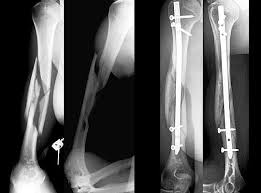

Upload Date: March 31, 2019 Full Size Image Dimensions: 261 × 193 Image Parent Post: Κατάγματα άνω άκρου

3b.Ενδομυελική ήλωση διάφυσης βρανιονίου